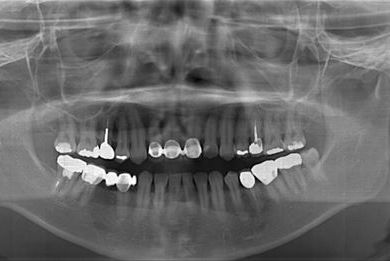

治療内容 メタルボンドセラミック(クラウン1本、ブリッジ3本、メタルボンドセラミック土台1本)+ハイブリッドセラミックインレー1本

治療部位

4

7 6 5 4

治療前

• 治療前